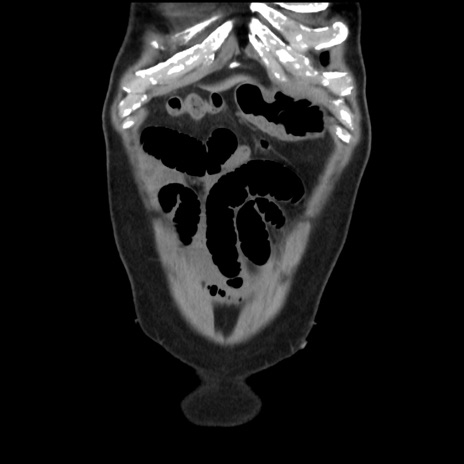

症例16(冠状断像)

【現病歴】 約1ヶ月前より間欠的に腹痛と嘔吐あり、当院消化器内科を受診したところCTで多発する肝臓のLDAを指摘され、精査中であった。以降は消化器症状は安定していたが、2日前より嘔気と腹痛があり、同日より排便・排ガスが消失した。改善認めず、 本日、救急外来を受診した。